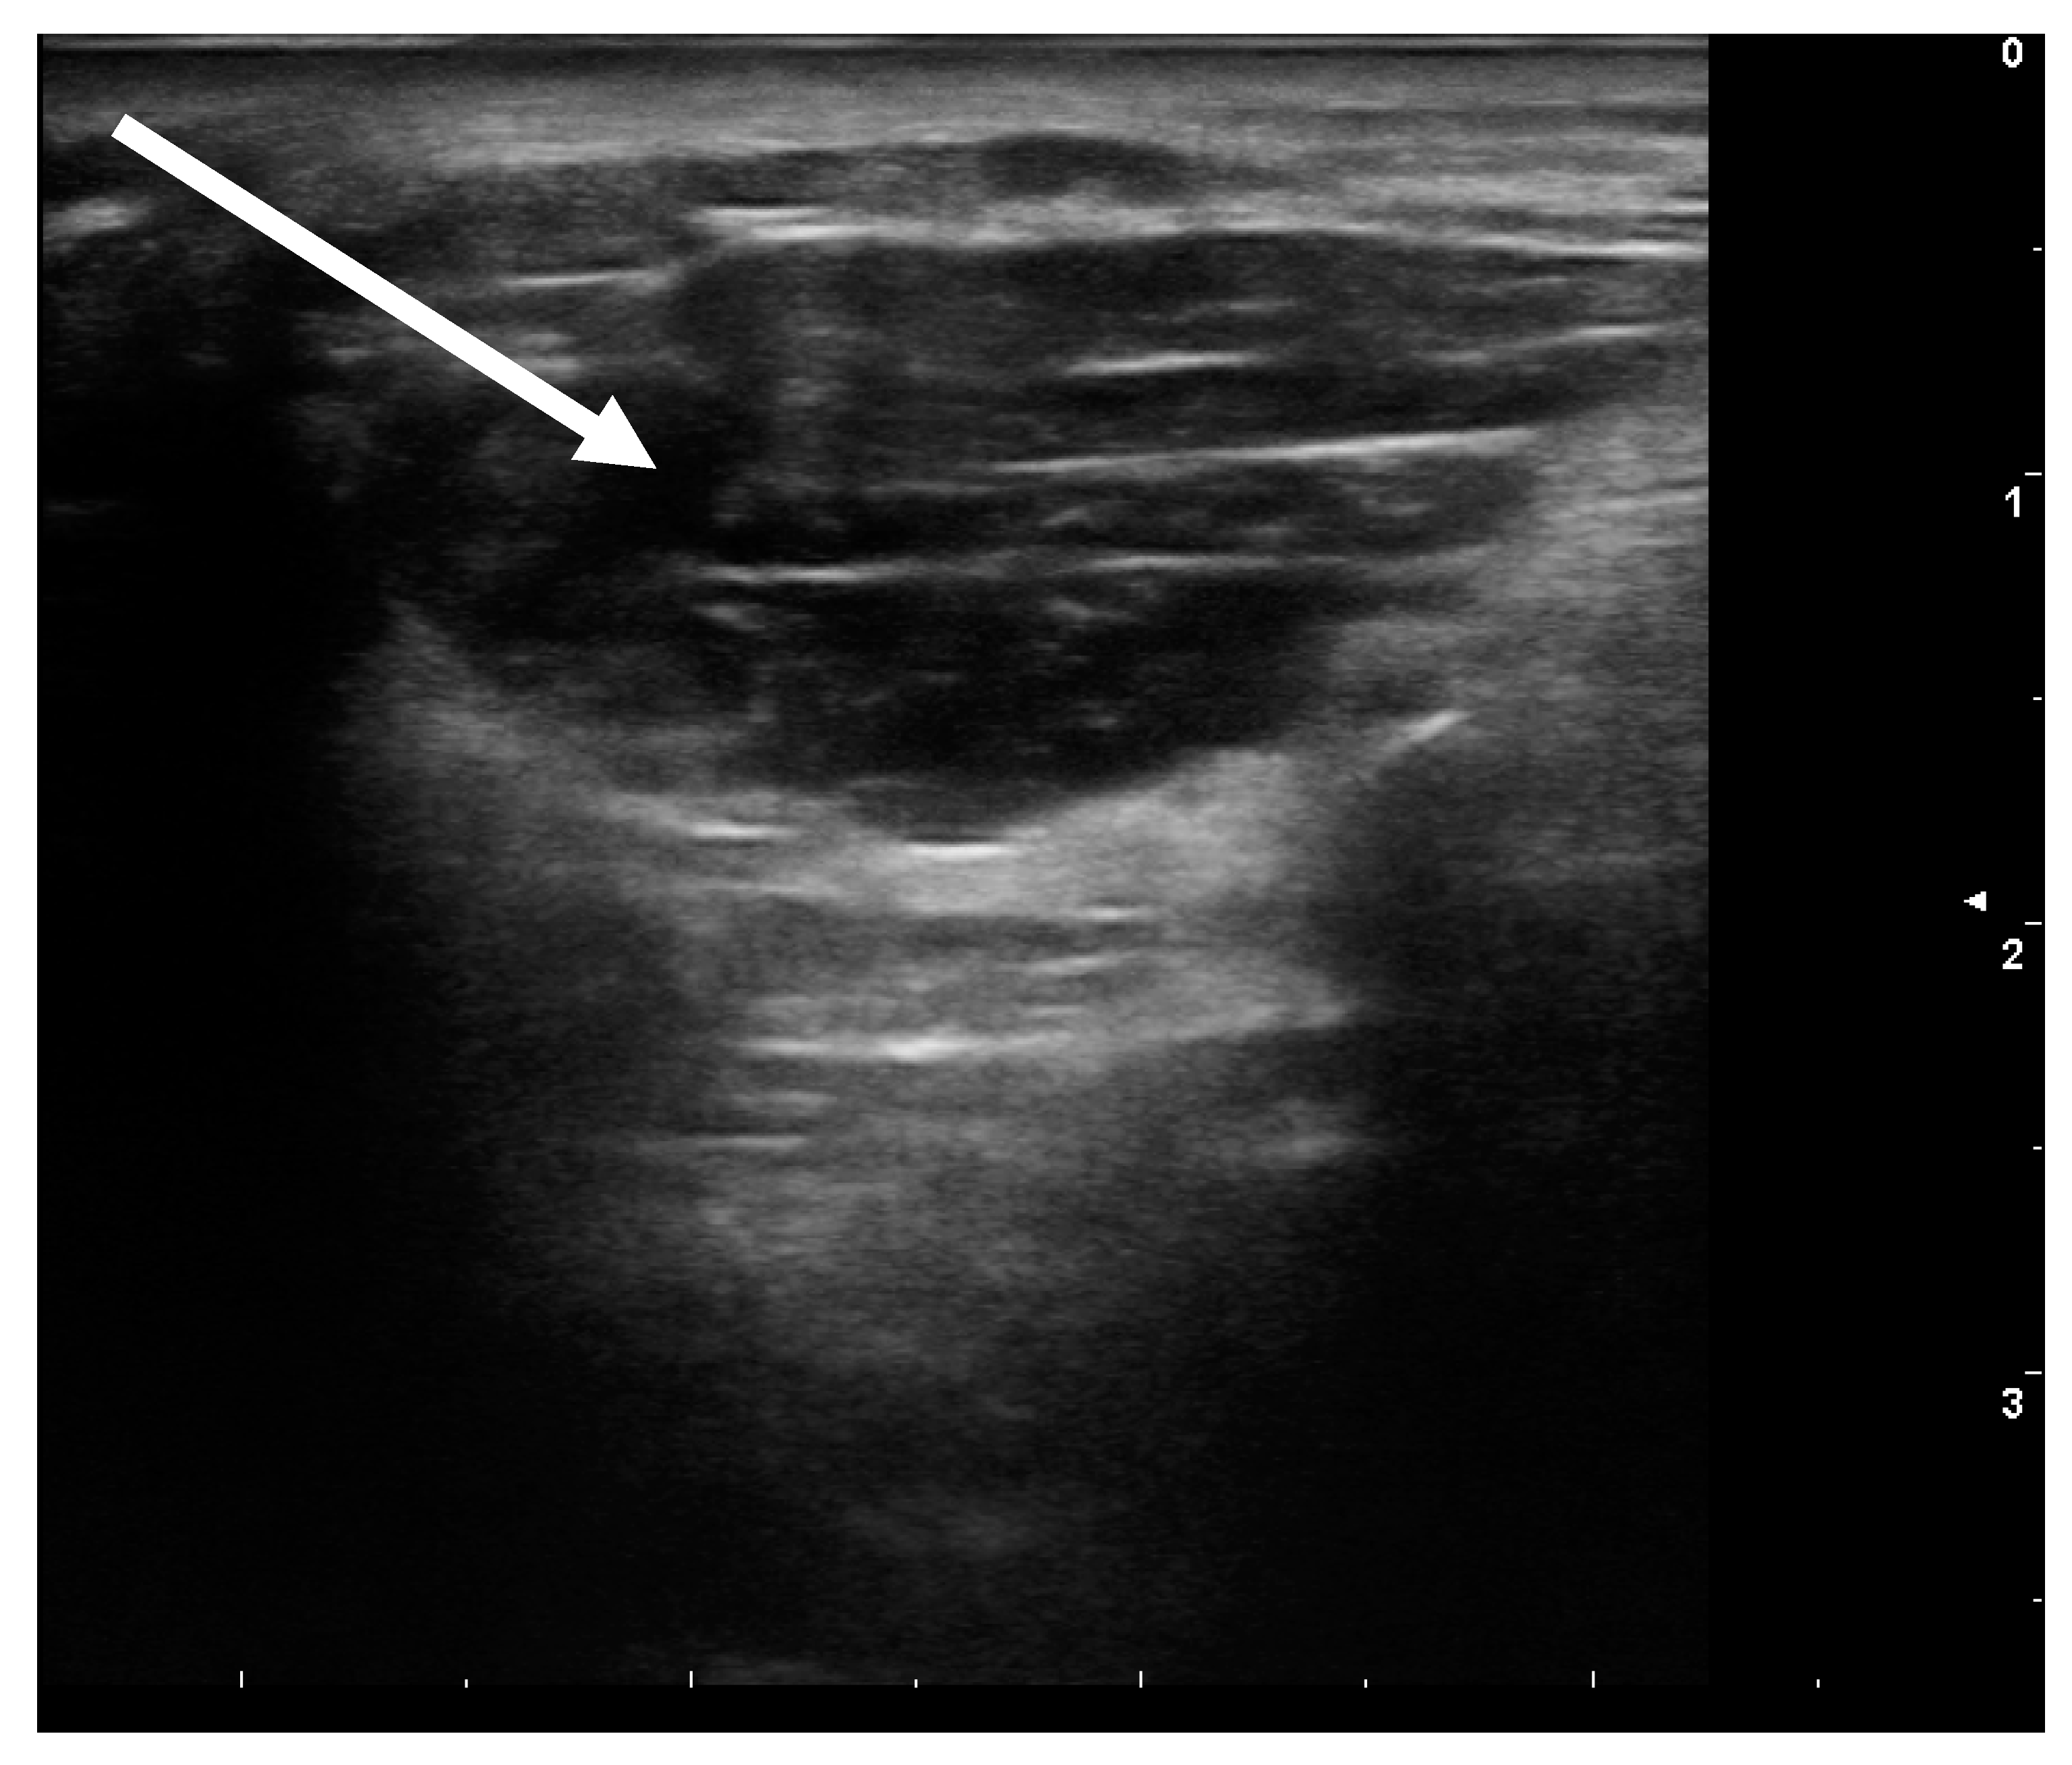

- Flexion of the toes:This second form usually causes more discomfort to the patients, as it induces involuntary movements in the toes, in particular the small ones, but also the big toes. It occurs frequently as exercise-induced dystonia. Here, a distinction has to be made whether only one of the two or both toe flexing muscles are involved. The short flexor is found in the sole of the foot, the long flexor in the lower calf. Here too the injection into the muscle is performed under ultrasonic guidance (see Figure 4).